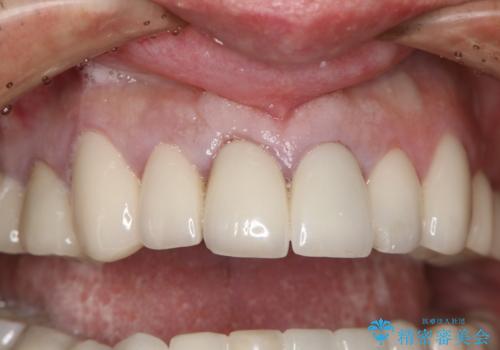

抜歯後早期インプラント埋入で術直後から噛める仮歯が入る!

- 事故による外傷で前歯に歯根が真っ二つに折れてしまい、保存不可能となってしまった部分にインプラント治療を計画しました。

患者様のご要望もあり、審美性の確保ができる抜歯早期埋入→埋入後即時荷重という手術法を取りました。

近年、インプラントの素材や手術法の研究が進み、保存不可能となった歯牙に対して抜歯してすぐインプラントを埋入し、さらに直後から仮歯がを入れ噛むことができる【抜歯即時埋入】【即時荷重】という技法が確立されました。

それと比較すると、今回の方法では骨にしっかりと固定されているインプラントに単独で仮歯を装着することができるためフロスも通せますし、ある程度負荷のかかる食事も気にせずできるようになります。